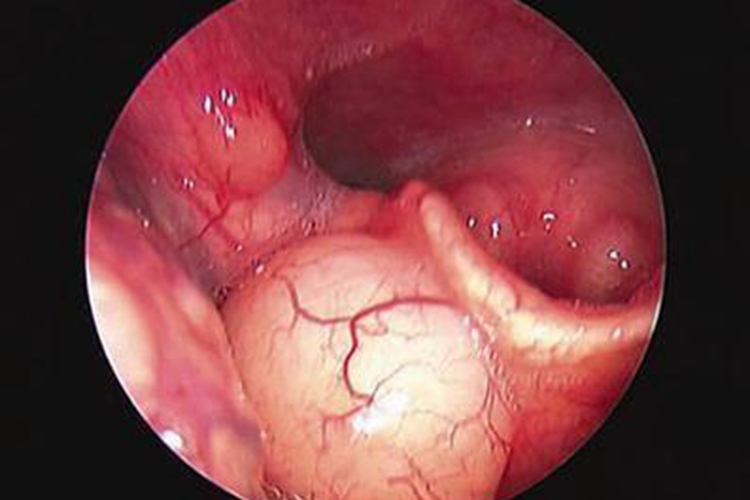

吃虾过敏者可出现皮肤症状,如发痒、发红、肿胀等。初期最先接触食物的口唇部可出现瘙痒、起红斑,逐渐扩展至全身皮肤,出现丘疹、丘疱疹、风团等症状;还可伴有喉咙瘙痒、喉头水肿、过敏性休克的症状。